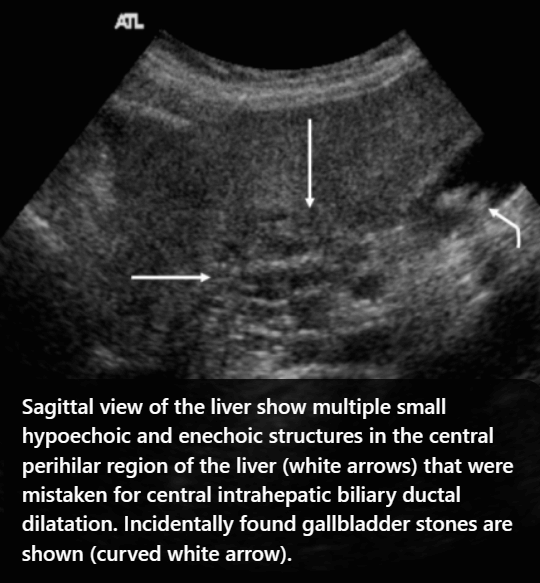

- 간문부와 직경이 큰 문맥관 주변에 호발 한다.

- portal vein을 따라 산재된 낭성병변 (포도송이 모양)